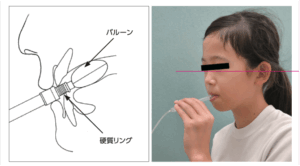

・人工乳首のタイプ(大きさ・形態・硬さ)による舌運動

・乳首の形状による1回の吸啜における舌運動の幅、持続時間